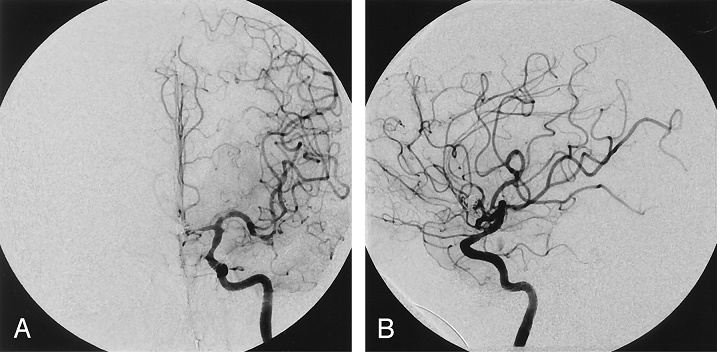

Chụp mạch quy ước (chụp mạch số hóa xóa nền- DSA)

DSA vẫn là tiêu chuẩn vàng để xác định các dạng tổn thương mạch não và bệnh lí.

B: Hình ảnh DSA mạch máu não của người bệnh sau khi can thiệp.